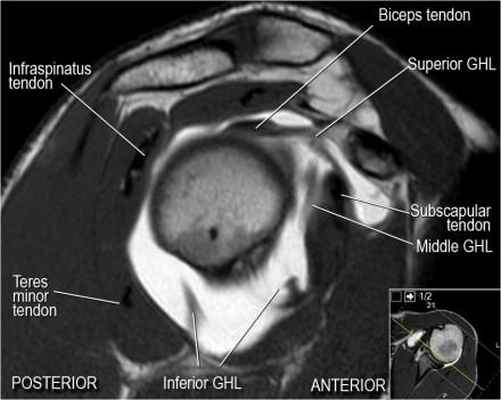

Нормальная анатомия плечевого сустава в аксиальных изображениях и контрольный список.

- обратите внимание что ход сухожилия длинной головки двуглавой мышцы в области прикрепления направлен на 12 часов. Область прикрепления может быть различной ширины.

- обратите внимание на верхние отделы суставной губы и прикрепление верхней плече-лопаточной связки. На данном уровне ищется SLAP-повреждение (Superior Labrum Anterior to Posterior) и варианты строения в виде отверстия под сутавной губой (sublabral foramen - подгубное отверстие). На этом же уровне по задне-боковой поверхности головки плечевой кости визуализируются повреждение Хилл-Сакса.

- волокна сухожилия подлопаточной мышцы, создавая бицепитальную борозду, удерживают сухожилие длинной головки двуглавой мышцы. Изучите хрящи.

- уровень средней плече-лопаточной связки и передних отделов суставной губы. Поищите комплекс Буффорда. Изучите хрящи.

- обратите внимание на волокна нижней плече-лопаточной связки. На данном уровне так же ищется повреждение Банкарта.